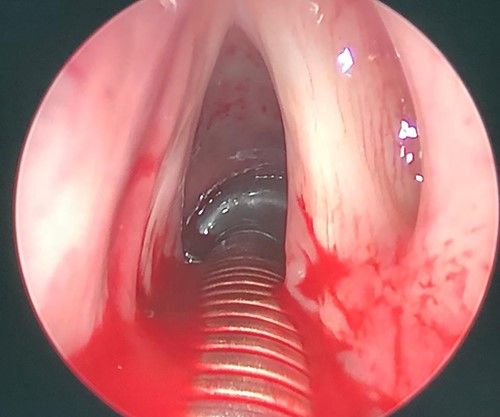

Flexible laryngoscopic examination of the larynx, showing left sided polypoidal mass.

A thorough otorhinolaryngology examination was done and revealed clear oral cavity as well as normal dental health condition. On flexible laryngoscopic examination, a 2 × 1-cm yellowish polypoidal mass covering left vocal cord was found with mild signs of reflux (Fig. 1).